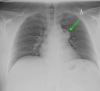

Mediastinal germ cell tumors are some of the less frequently encountered anterior mediastinal masses. We report an interesting case of a 26-year-old male with a ruptured mediastinal cystic teratoma. Initial plain radiograph and CT scan of the chest showed radiographic evidence of a ruptured cystic teratoma, including a peripherally enhancing, partially calcified mass with internal fat density. Upon surgical excision, the mass was found to adhere to the thymus and anterior aortic arch. The patient was promptly diagnosed via imaging and managed in a timely manner via complete surgical resection.